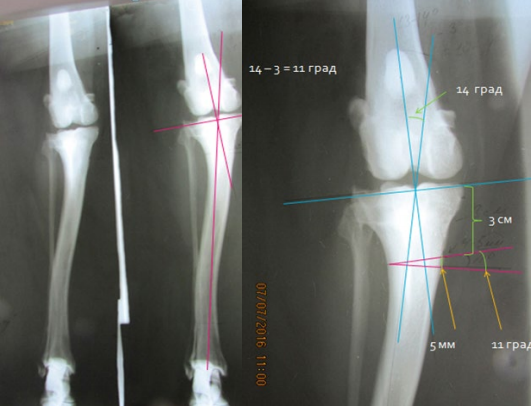

Рекурвация коленного сустава: рентгеновские снимки и объяснения